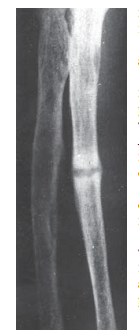

8.4 сурет. Біріншілік гиперпаратиреоз кезіндегі білек рентгенограммасы: фалангалардың субпериостальды резорбциясы

4. Сүйектік өзгерістер: остеопороз, хондрокальциноз; ауыр БГП: субпериостальды резорбция, білек, аяқ фалангаларының акроостеолизі (сурет 8.4), қаңқа деформациясы, сүйектердің патологиялық сынықтары (8.5 сурет), кисталар, алыпжасушалық ісіктер және эпулидтер (кисталық түзілістер).